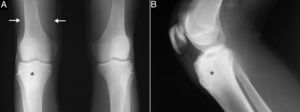

A 15-year-old boy presented with an 8-month history of mechanical pain in right knee. It would be intermittent at first and later become continuous, making it difficult for him to walk, and swelling was observed in that area. The treatment consisted of nonsteroidal anti-inflammatory drugs (NSAID), initially ibuprofen, which was replaced by diclofenac, but there was no improvement. He had no history of injury, fever or constitutional symptoms, or manifestations affecting any other peripheral or axial joint or enthesitis. He had been diagnosed with guttate psoriasis at the age of 10 years, with occasional episodes until he was 13, and was treated with topical glucocorticoids; however, he had no family history of psoriasis, psoriatic arthritis, ankylosing spondylitis or inflammatory bowel disease. Physical examination revealed muscle atrophy in distal thigh and swelling in right infrapatellar region, which was warm, and he had a limitation in last few degrees of flexion, but with no signs of joint effusion. The results of laboratory tests, including biochemical analyses, complete blood count and acute-phase reactants (erythrocyte sedimentation rate 6mm/h, C-reactive protein 2.31mg/dL) were normal. Human leukocyte antigen (HLA) typing revealed the presence of Cw6, DR4 and DQ8 haplotypes, but not B27, and the patient was negative for rheumatoid factor and antinuclear antibodies. Plain radiography of the knees showed a sclerotic area in the upper third of right tibia (Fig. 1A and B), which, according to computed tomography (CT), corresponded to an osteolytic lesion measuring 5mm in diameter in anterior tibial tuberosity, with a “nidus” formed by an ossified matrix, compatible with OO (Fig. 2B and C), with extensive sclerosis of the medullary bone and a solid periosteal reaction in the adjacent cortical bone. Magnetic resonance revealed intense contrast uptake in and around the lesion, as well as in the surrounding bone edema and the Hoffa fat pad (Fig. 2C and D). Bone scintigraphy disclosed hyperemia and a focal increase in the osteogenic response in the proximal epiphysis of right tibia, with no other significant changes. The patient underwent CT-guided radiofrequency ablation, and the pain disappeared a few days after the procedure, and he recovered complete mobility 1 month later, although he had mild persistent muscle atrophy.

Sagittal (A) and axial (B) computed tomography images of right knee showing an osteolytic lesion in the subendosteal region of the anterior tibial tuberosity, with a “nidus” formed by ossified matrix, compatible with osteoid osteoma (arrow), encircled by extensive sclerosis of the surrounding medullary bone (asterisks) and a solid periosteal reaction in the adjacent cortical bone (arrowheads). Post-gadolinium sagittal (C) and axial (D) T1-weighted spectral presaturation with inversion recovery (STIR) magnetic resonance images revealed perilesional contrast uptake in the form of a ring (arrow), and in surrounding bone edema (asterisks) and Hoffa fat pad (arrowheads).